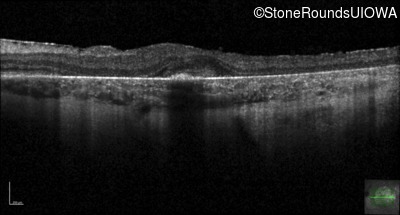

Age at visit: 30 years

This 30 year old man first noticed poor vision in dim light when he was five years old. His visual acuity began to fall in his early 20's.

Age at visit: 32 years

Age at visit: 34 years

Age at visit: 35 years

Age at visit: 37 years

Age at visit: 39 years

Age at visit: 40 years

Age at visit: 42 years